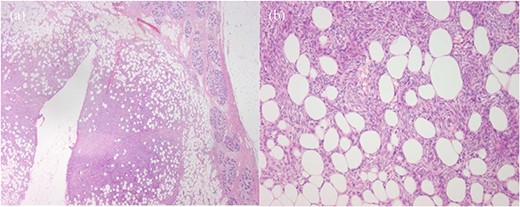

Histopathology showed a 10 × 10 mm tumour composed of bland and crumpled spindle cells with a storiform arrangement showing a honeycomb pattern of infiltration into the surrounding adipose tissue (Fig. 3). There was minimal mitotic activity and only mild cytological atypia. The lesion had strong expression of CD34 whilst a range of keratin stains (HMWCK, CAM 5.2, CK 5/6, CK14, and AE1/AE3) were negative. There was no involvement of the skin seen. This is consistent with a DFSP of the breast, with intramammary subtype. The excision margins were clear, with the closest being 12 mm from the superficial margin, and ˃20 mm from all other margins. There was a background of widespread secretory and lactational change of the breast consistent with pregnancy, and an incidental single focus of atypical ductal hyperplasia seen.

Histopathology, (a) Haematoxylin and eosin (H&E)-stained section of breast parenchyma showing lactational change and containing an ill-defined spindled cell tumour and a central defect from localisation wire. (b) H&E section of tumour with bland spindled cells in tight storiform arrays that infiltrate and entrap adjacent adipocytes (fat), producing a honeycomb pattern.

Diagnosis with core biopsy is crucial as histopathologically DFSPs have a characteristic appearance with storiform architecture, infiltrative ‘honeycomb’ growth within subcutaneous adipose tissue, and immunoreactivity for CD34. In total, ˃90% of cases are associated with translocation of COL1A1-PDGFβ fusion product. A variant mutation of COL6A3-PDGFD fusion product has been shown to have a predilection for breast DFSPs [1, 5], however detection of this translocation is limited in the clinical setting.